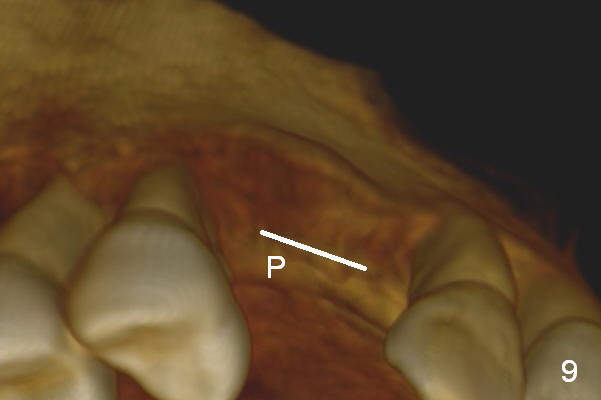

Retrospectively, bone expansion should have been initiated (Fig.9 white line) close to the thicker palatal plate (P). The coronal end of the osteotomes should have been directed palatally. It would be much better to use a D implant (Fig.10).